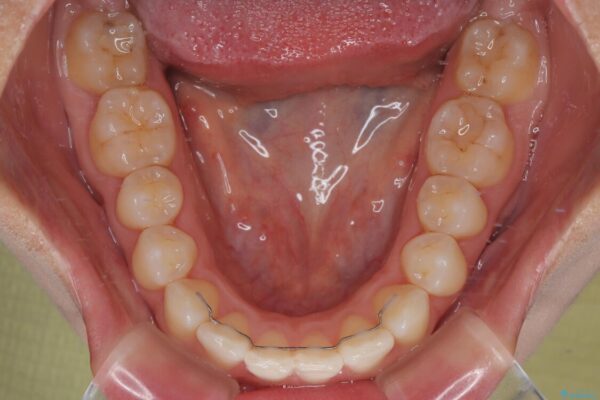

治療終了時

前歯が自然なアーチにきれいに並び、正中(上下の中心線)も整い、咬み合わせも良好です。

側方拡大することで、非抜歯であるにも関わらず前歯が前方に出ることなく、バランスの良い仕上がりとなりました。

治療後

• 目立ちにくい表側装置で1年完了!狭いアーチを側方拡大し前歯のデコボコを整えた症例 治療後画像